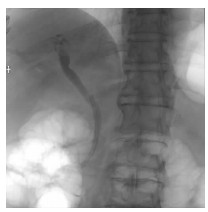

内镜逆行胰胆管造影术后并发肝包膜下血肿1例报告

罗宜辉

2021, 37(8): 1914-1915. DOI: 10.3969/j.issn.1001-5256.2021.08.035

摘要(776) HTML (250) PDF (1901KB)(55)

摘要: